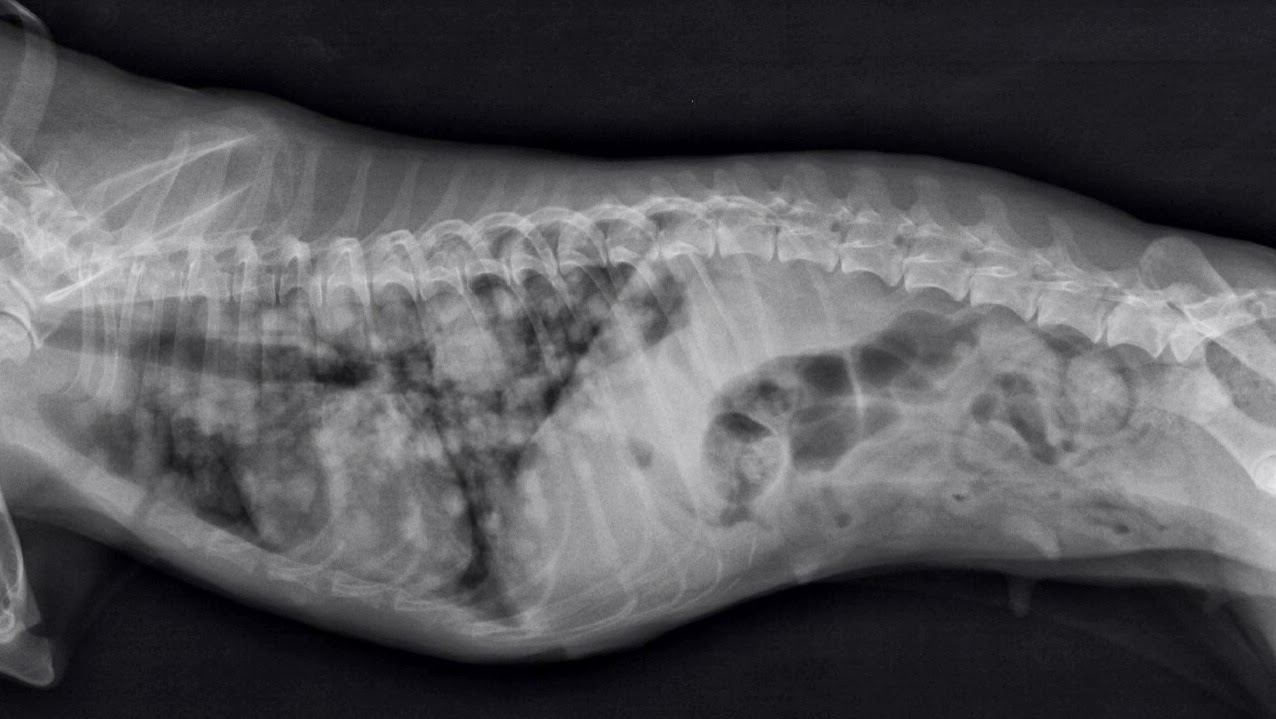

Mi Perro Tiene Metastasis En Los Pulmones, , , , , , , 0, Mi Perro Tiene Metastasis En Los Pulmones - Noticias del Perro, esperronoticias.blogspot.com, 1276 x 719, jpeg, WebEl segundo tipo de cáncer de pulmón en perros se llama cáncer de pulmón metastásico, lo que significa que el cáncer se originó en otro lugar del cuerpo, pero se diseminó hasta el. WebBaje la cabeza del cachorro para ayudar a drenar el líquido de sus pulmones, boca y garganta. Coloque una perilla de succión dentro de la boca y la nariz del cachorro para., 20, mi-perro-tiene-metastasis-en-los-pulmones, Novedades y Muebles WebEl segundo tipo de cáncer de pulmón en perros se llama cáncer de pulmón metastásico, lo que significa que el cáncer se originó en otro lugar del cuerpo, pero se diseminó hasta el. WebBaje la cabeza del cachorro para ayudar a drenar el líquido de sus pulmones, boca y garganta. Coloque una perilla de succión dentro de la boca y la nariz del cachorro para.

WebEn perros y gatos, los tumores de los lóbulos del pulmón (“pulmonares”) se producen casi siempre por células cancerígenas que ha transportado el torrente sanguíneo y han. Webcomo te dice Xiliona, metástasis y me pongo en lo peor. Mora fue operada, le quitaron 2 tetillas y un tumor del tamaño de un grano de arroz. 5 años después me dijeron que se.

Tumores de mama. Metástasis pulmonares. | Diagnóstico Veterinario

Source: www.diagnosticoveterinario.com